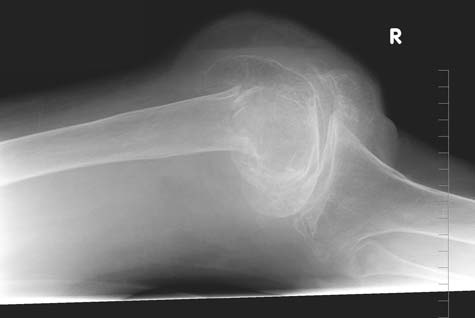

Imagen sencilla por rayos X de la rodilla de un paciente que muestra médula grasosa en el espacio articular.

Nota: Las imágenes se muestra para fines ilustrativos. No trate de sacar conclusiones comparando esta imagen con otras en el sitio. Solamente los radiólogos calificados deben interpretar las imágenes.